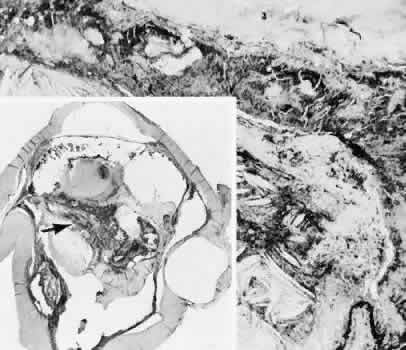

Descemet's membrane is only loosely adherent to the posterior stroma and may be stripped into the anterior chamber at the time of the corneal incision placement (Fig. 27) or injection of sodium hyaluronate. Splitting off of Descemet's membrane from the posterior cornea can lead to postoperative intractable corneal edema.89,90

Fig. 27. A case of stripping of Desce-met's membrane during a filteringprocedure (scleral cautery and iridectomy). A. The clinical appearance was one of extensive filtering bleb formation superiorly and regional dense corneal edema and opacification. B. The anterior chamber remains formed. Detached Descemet's membrane can be seen protruding into the anterior chamber. The patient died shortly after surgery from unrelated causes.C. The gross appearance of the area of detached Descemet's membrane extending into the anterior chamber.D. On the histologic section, the origin of detached Descemet's membraneextends to the region of the limbal wound. (Hematoxylin-eosin stain; × 16.) (Kozart DM, Eagle RC Jr: Stripping of Descemet's membrane after glaucoma surgery. Ophthalmic Surg 12:420–423, 1981.)